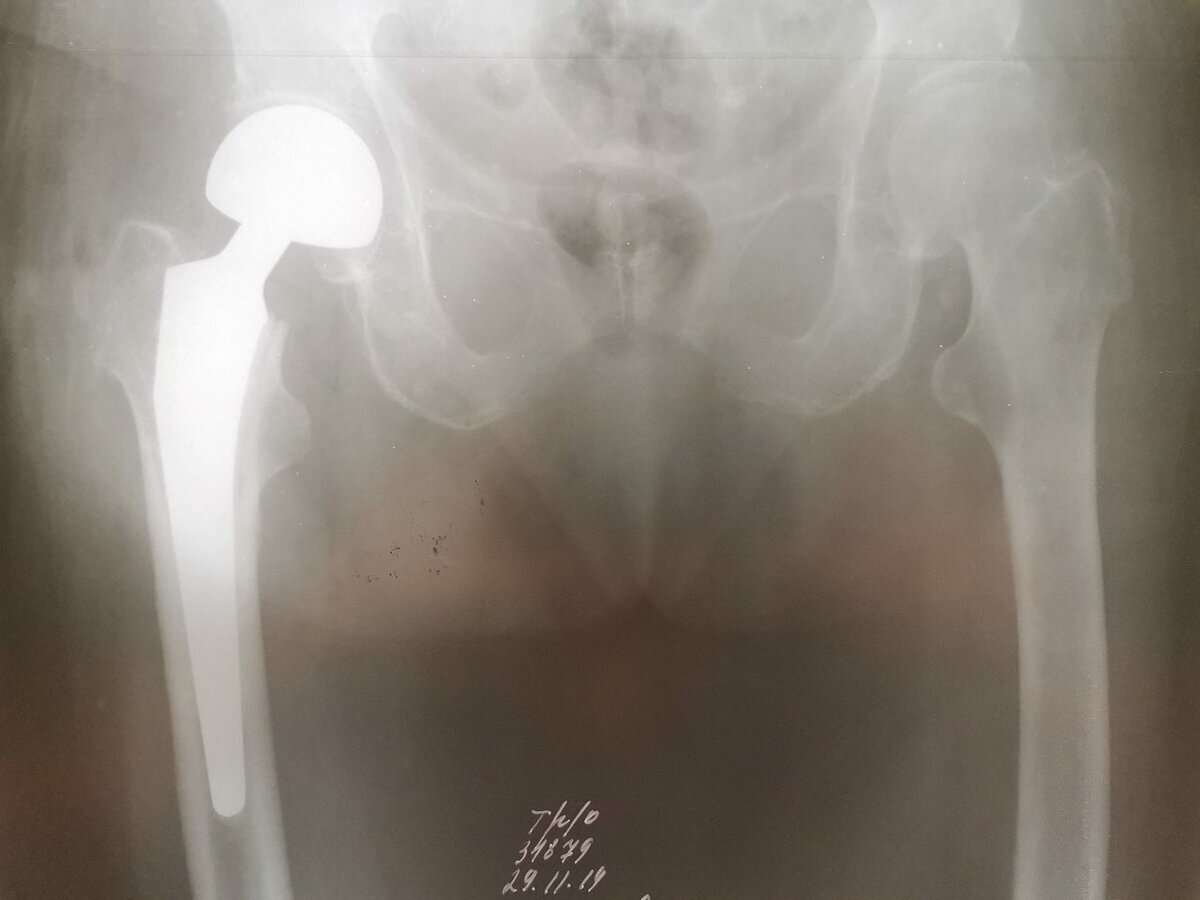

Здравоохранение: квота на эндопротезирование